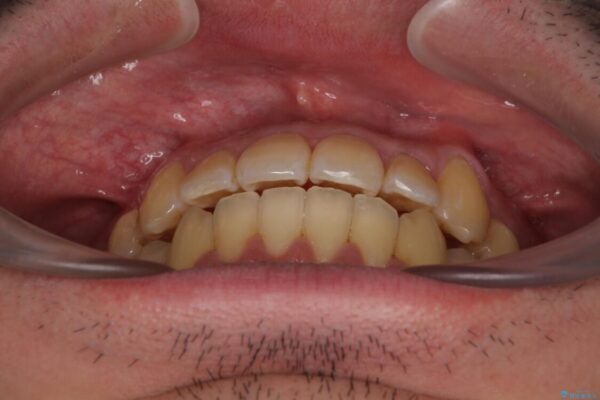

八重歯と前歯のクロスバイトを改善したいとのことで来院された患者様です。

デコボコの程度は強かったのですが、口元の突出感はなかったため、非抜歯矯正としました。

治療前

• 八重歯とクロスバイト 目立たないワイヤー装置で矯正治療 治療前画像